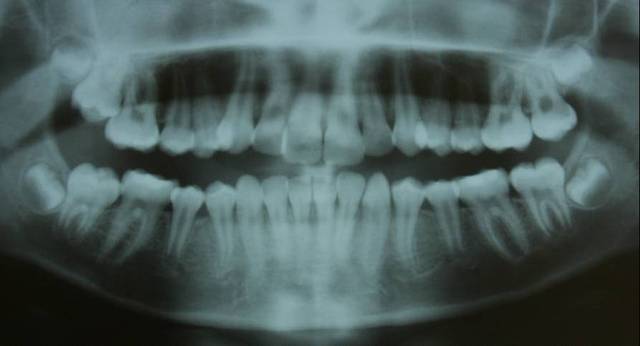

Je crois cette fois ca va marcher. Il s'agit d'une jeune fille de 12 ans, origine franco-libanaise, deja reglee depuis qqs mois. Classe II1 dentaire. Une demande majeure pour la patiente et sa maman: Les dents du haut sont trop en avant, il ne faut surtout pas les avancer ou les garder comme ca!!!

classe II squelettique(responsabilite mandibulaire),cl II dentaire,petite ddm,constriction de arc sup,flaring des incisives sup,face moyenne etroite,mesiodivergent

legere deviation des milieux

demande esthetique